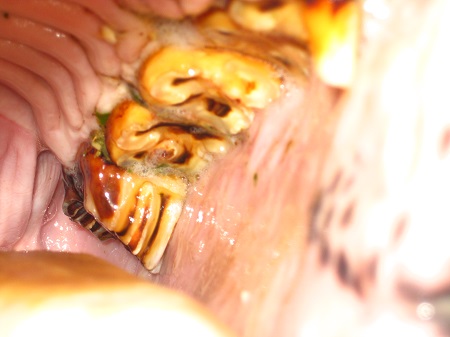

Die weitaus häufigsten Erkrankungen beim Esel sind Zahnerkrankungen. Dabei kommt es häufig vor, dass sogar schwerwiegende Zahnerkrankungen nicht erkannt werden, da der Esel keine Veränderungen bei der Nahrungsaufnahme zeigt. Tatsächlich ist es aber so, dass Esel die Futteraufnahme erst im hochgradigen Stadium bei unerträglichen Schmerzen einstellen. Eine regelmäßige sorgfältige Zahnkontrolle ist somit auch beim scheinbar gesunden Esel unerlässlich.

Der Esel unterscheidet sich in der Zahnanatomie und ‑histologie nicht wesentlich vom Pferd. Die Zähne des Esels sind hypsodont mit einem apikalen und einem koronalen Bereich, wobei der größte Teil der Zahnkrone als Reservekrone in der Alveole liegt. Der Esel hat 36–44 permanente Zähne, abhängig von der Ausbildung der Wolfszähne oder Canini. Zur Nummerierung und Identifikation der Zähne hat sich beim Esel das modifizierte Triadan-System nach Floyd bewährt.

Erkrankungen der Backenzähne

Im Bereich der Backenzähne sind die häufigsten Ursachen für Zahnprobleme:

- scharfe Zahnkanten

- fehlerhafte oder mangelnde Abnutzung der Backenzähne mit Bildung eines Stufen- oderWellengebisses

- pathologische Veränderungen des bukkolingualen Zahnwinkels

Dies kann zu schmerzhaften Verletzungen der Maulschleimhaut und der Zunge und zu Problemen beim Kauvorgang führen. Die Backenzähne sollten regelmäßig kontrolliert und ggf. durch Einschleiftherapie mit manuellen oder elektronischen Zahnraspeln korrigiert werden.

Sehr schmerzhaft sind Parodontaltaschen im Bereich der Backenzähne mit oder ohne Futtereinspießung. Sie entstehen durch die Lockerung, das Verkippen, das Verdrehen oder die Wanderung benachbarter Backenzähne und können im schlimmsten Fall zum Verlust betroffener Zähne führen. Die Therapie gleicht der beim Pferd.